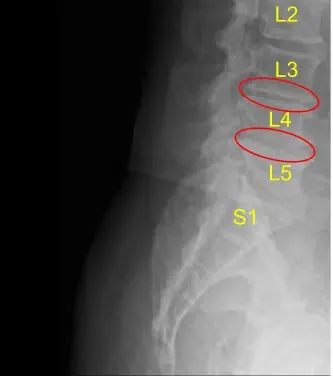

La resonancia magnética y la tomografía computarizada de la columna lumbar mostraron una grave ruptura degenerativa del espacio discal en L3-L4 y L4-L5, por lo que se les ofreció una cirugía para el dolor discogénico. Se explicaron extensamente los riesgos y posibles beneficios de la cirugía al paciente.

El espacio del disco se estrecha en L3-L4 y L4-L5

Protuberancia discal y artropatía facetaria

Firmaron el consentimiento informado y fueron llevados al quirófano para el procedimiento mencionado. Los hallazgos de la radiografía preoperatoria de la columna lumbar se muestran arriba y los pacientes también se sometieron a una tomografía computarizada preoperatoria (TAC) que se muestra arriba.